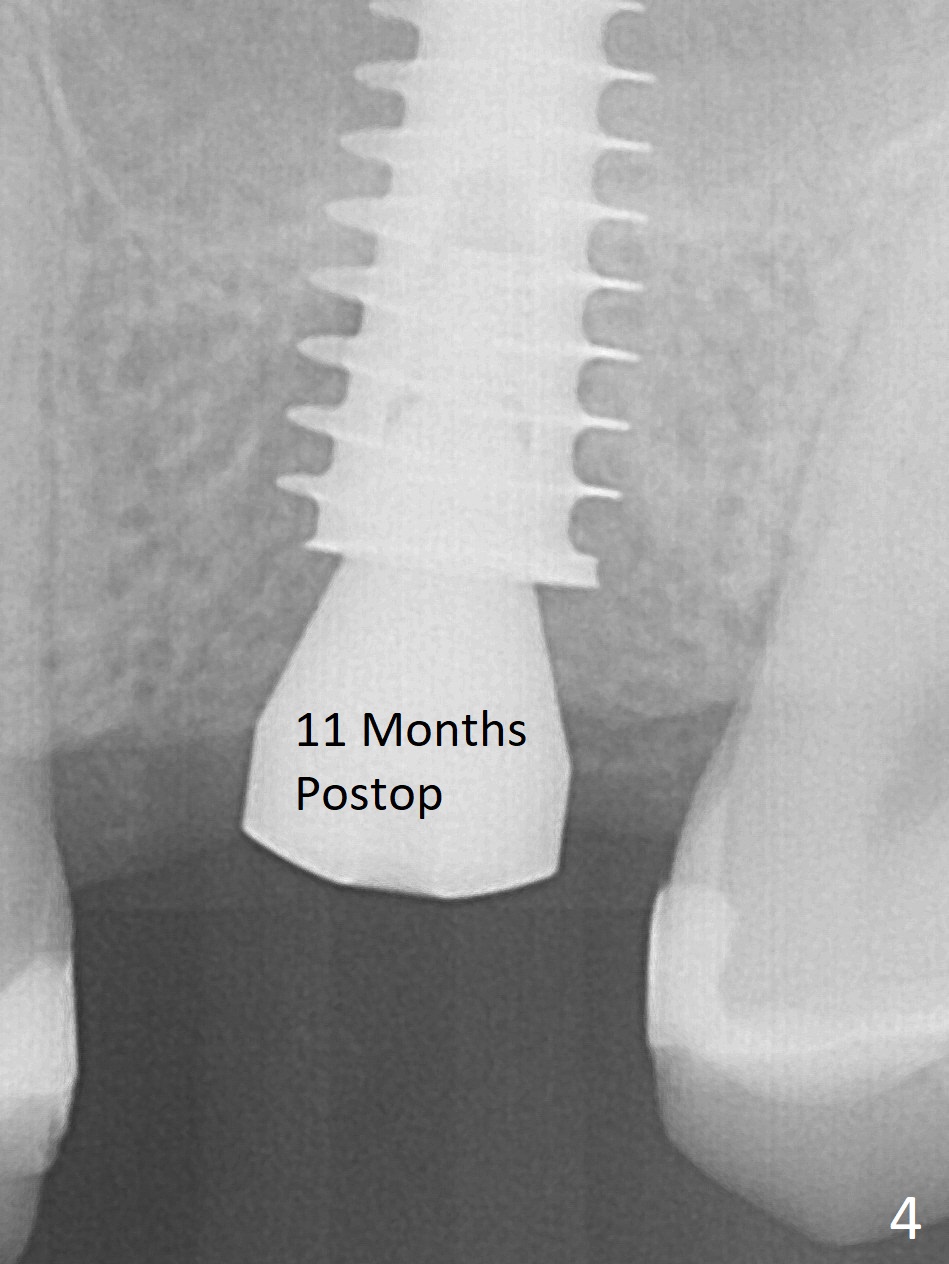

After extraction of the tooth #14 with palatal swelling (Fig.1 *), the septum (S in Fig.2) is found to be thin. Sequential osteotomy quickly deviates to the palatal socket. In spite of using Lindamann bur to remove the bone from the buccal portion of the osteotomy, the apical end of a 5x9 mm dummy implant slides into the palatal socket with the coronal end placed as buccal as possible for restoration (Fig.2 (poor trajectory)). Further use of Lindamann bur for buccal bone removal is not feasible, since the buccoapical portion of the osteotomy starts to be perforated with apparently intact sinus membrane. With insertion of Vanilla graft for sinus lift through the buccoapical portion of the osteotomy mentioned above, a 6x11 mm implant is placed with the same trajectory (Fig.2, <40 Ncm). With placement of a 6.5x4(3) mm abutment (off angle) and of Vanilla graft in the remaining sockets (Fig.2 *), periodontal dressing is applied. When the dressing is dislodged for the 2nd time (12 days postop with healing socket), an angled abutment 5x15 degree, 3 mm cuff, is placed and a provisional is fabricated. There is no sign of sinus infection. The provisional and angled abutment become loose without sinus infection 2 months postop. A 5.5x3 mm healing abutment is placed with light tenderness. If this case turns to be failure, do not stick an immediate implant from potentially infected socket into the sinus in the future. The socket appears to heal 11 months postop (Fig.4). Later a 5x4(3) mm abutment is placed for final restoration. The palatal margin is low. The abutment screw is loose <2 months post cementation, probably due to deep placement and poor trajectory (buccal). It becomes loose again 4 months later. Prior to retightening, a 6 mm profile drill is used. BW shows no bony interference (Fig.5 (opposing tooth occlusal wear; bruxism)), while PA shows the buccal bone, suggesting poor trajectory. The abutment is loose for the 3rd time 17 months post cementation. When the crown/abutment is removed, the hex is worn. After proximal reduction, the crown/abutment feels to be unable to be re-seated. When the crown is sectioned, the abutment itself is incompletely seated (Fig.7,8). The mesial crest appears to interfere with seating (Fig.8). When the 5.2x3 mm dummy abutment is seated, the buccal margin is subgingival, while the palatal one supragingival, suggesting the buccally tilted implant (guided surgery essential). A 4.5x4(4) mm pair abutment seems to be seated completely (Fig.9). The hex of the 5x4(3) mm abutment is worn, but the abutment seems to be able to be seated completely (Fig.11), although not so crisply (easily) as the unworn one clinically. Return to Upper Molar Immediate Implant, Prevent Molar Periimplantitis (Protocols, Table), Armaments Screw Xin Wei, DDS, PhD, MS 1st edition 06/26/2018, last revision 12/20/2020